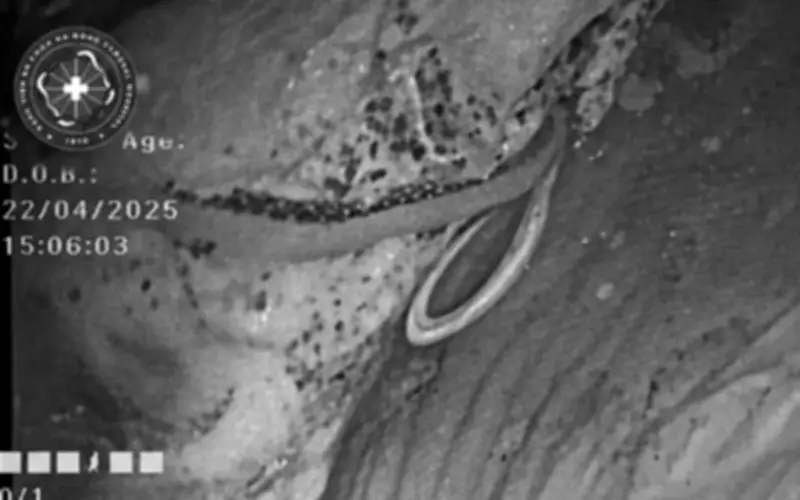

Mới đây, bệnh nhân N.T.H. (47 tuổi) nhập Bệnh viện Đa khoa Hà Đông trong tình trạng đầy bụng, khó tiêu kéo dài, kèm rối loạn đại tiện và mệt mỏi không rõ nguyên nhân. Trong quá trình nội soi đại tràng, bác sĩ chuyên khoa II Nguyễn Hợp, phụ trách Trung tâm Nội soi, bất ngờ phát hiện một hình ảnh bất thường: một ký sinh trùng dạng sợi trắng, dài, đang cuộn trong lòng ruột. Đây được xác định là nguyên nhân trực tiếp gây ra các triệu chứng kéo dài ở bệnh nhân.

Ngay sau đó, các bác sĩ tiến hành đánh giá mức độ nhiễm, xác định loại ký sinh trùng và tình trạng tổn thương niêm mạc ruột. Bệnh nhân được chỉ định điều trị bằng các thuốc tẩy giun thông dụng như Albendazole hoặc Mebendazole, đồng thời được tư vấn kỹ về vệ sinh ăn uống, sinh hoạt nhằm hạn chế nguy cơ tái nhiễm.